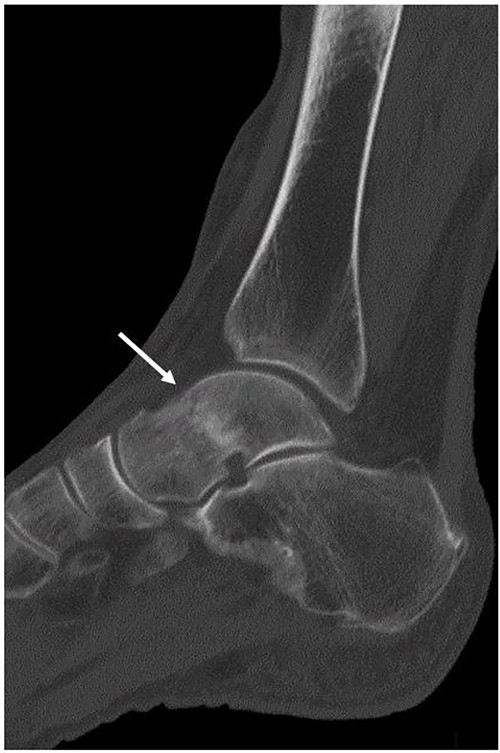

Although a non-contrast CT scan of the sagittal view demonstrated a fracture line in the talar neck (arrow), the bone fragment was not dislocated.